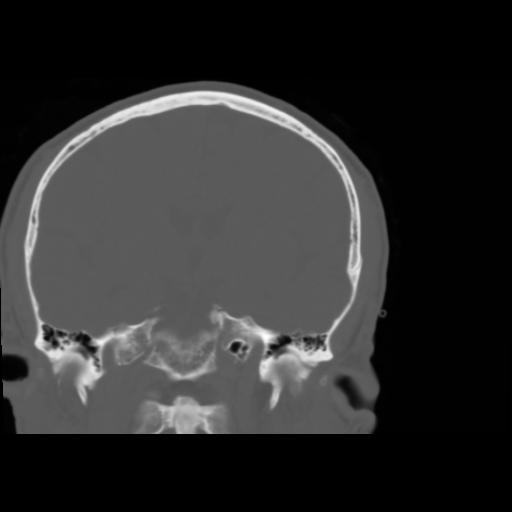

5 CEREBRO,,Coronal,3.000,CEREBRO,Coronal,